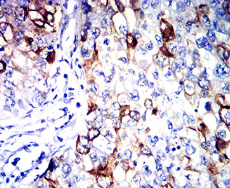

CDKN1A Mouse Monoclonal antibody[2B7F8]

IHC    1/200 - 1/1000